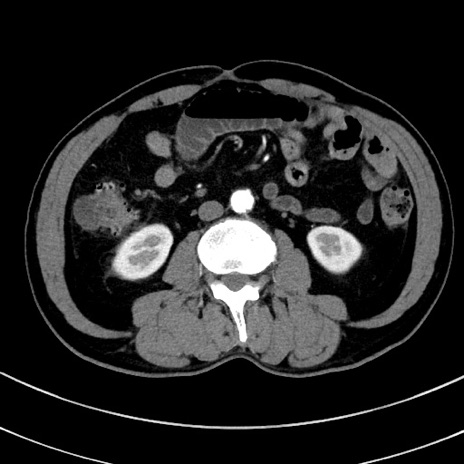

症例8(横断像)

【症例】 60歳代男性

【主訴】 黒色吐物

【現病歴】 4日前から嘔気自覚、2日前の朝食後にも嘔気あり、自分で手で嘔吐反射起こし嘔吐したところ血が混ざっていたため受診。

【既往歴】 5年前汎発性腹膜炎を伴う急性虫垂炎で手術、高血圧、前立腺肥大症、高脂血症

【身体所見】 腹部正中に手術癩痕あり 腹部平坦・軟圧痛なし膨満感あり

【データ】WBC 8400、CRP 4.54